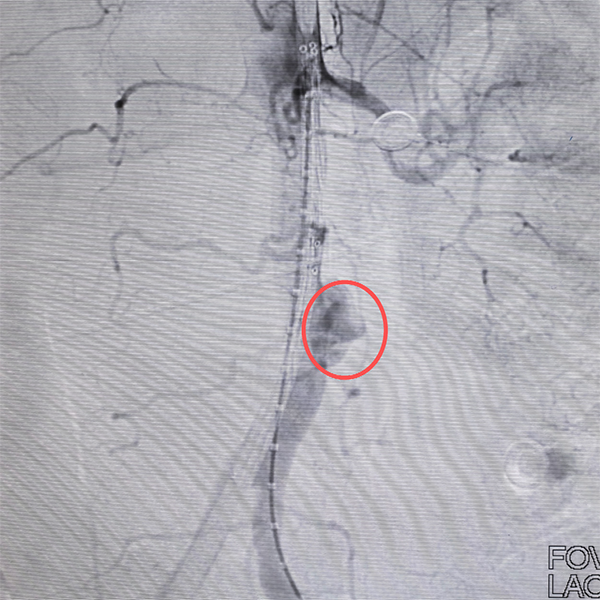

“虽然患者疼痛不剧烈,但同样是结核,同样是肾衰竭,同样有腹部不适……这不是简单的巧合!”前一天连夜抢救孙大伯的经历,立刻引起了明湘虹副主任医师的高度警觉。果然,腹部增强CT检查结果印证了她的判断:患者腹主动脉局部造影剂外溢形成假性动脉瘤样改变——同样是腹主动脉破裂假性动脉瘤形成,所幸发现及时!

术前

又是一个凌晨,喻四龙主任团队再次上阵,为李大伯实施了手术。由于发现及时,这颗“地雷”被及时清除。术后,两位患者症状均明显好转,正在顺利恢复中。